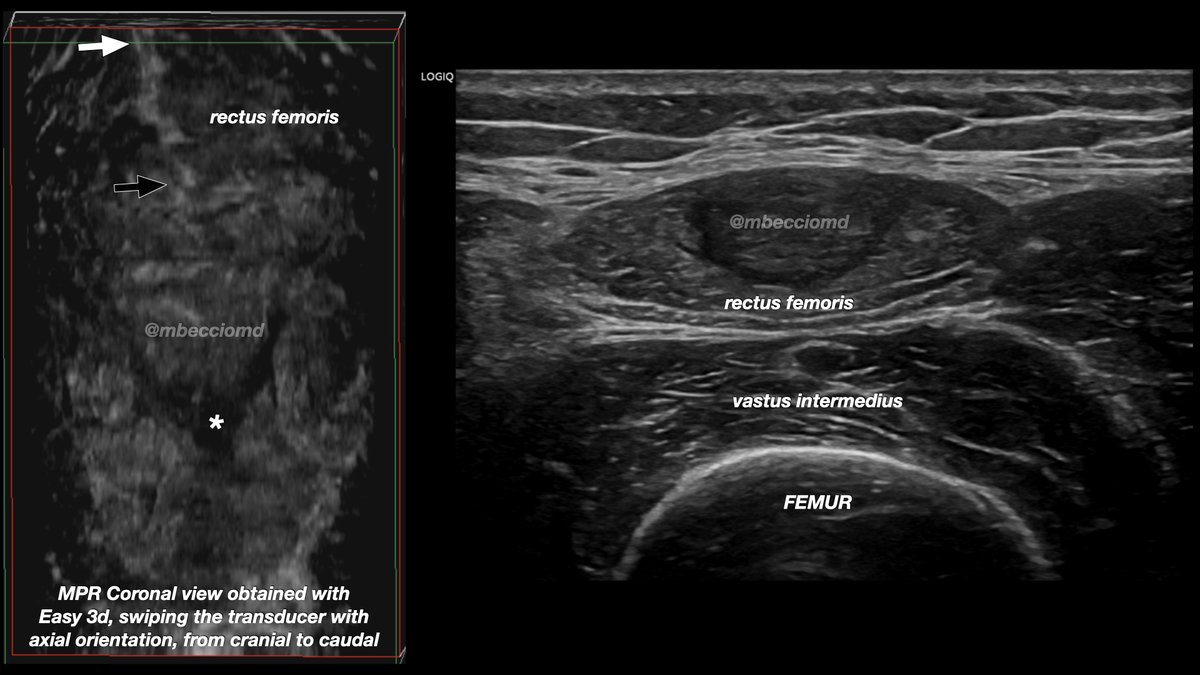

Medical Doctor @AlNassrFc /Ex @atleti y @caracas_FC /Real Federación Española de Futbol/ CEMTRO Clinic/ Sports Medicine Complutense University of Madrid /